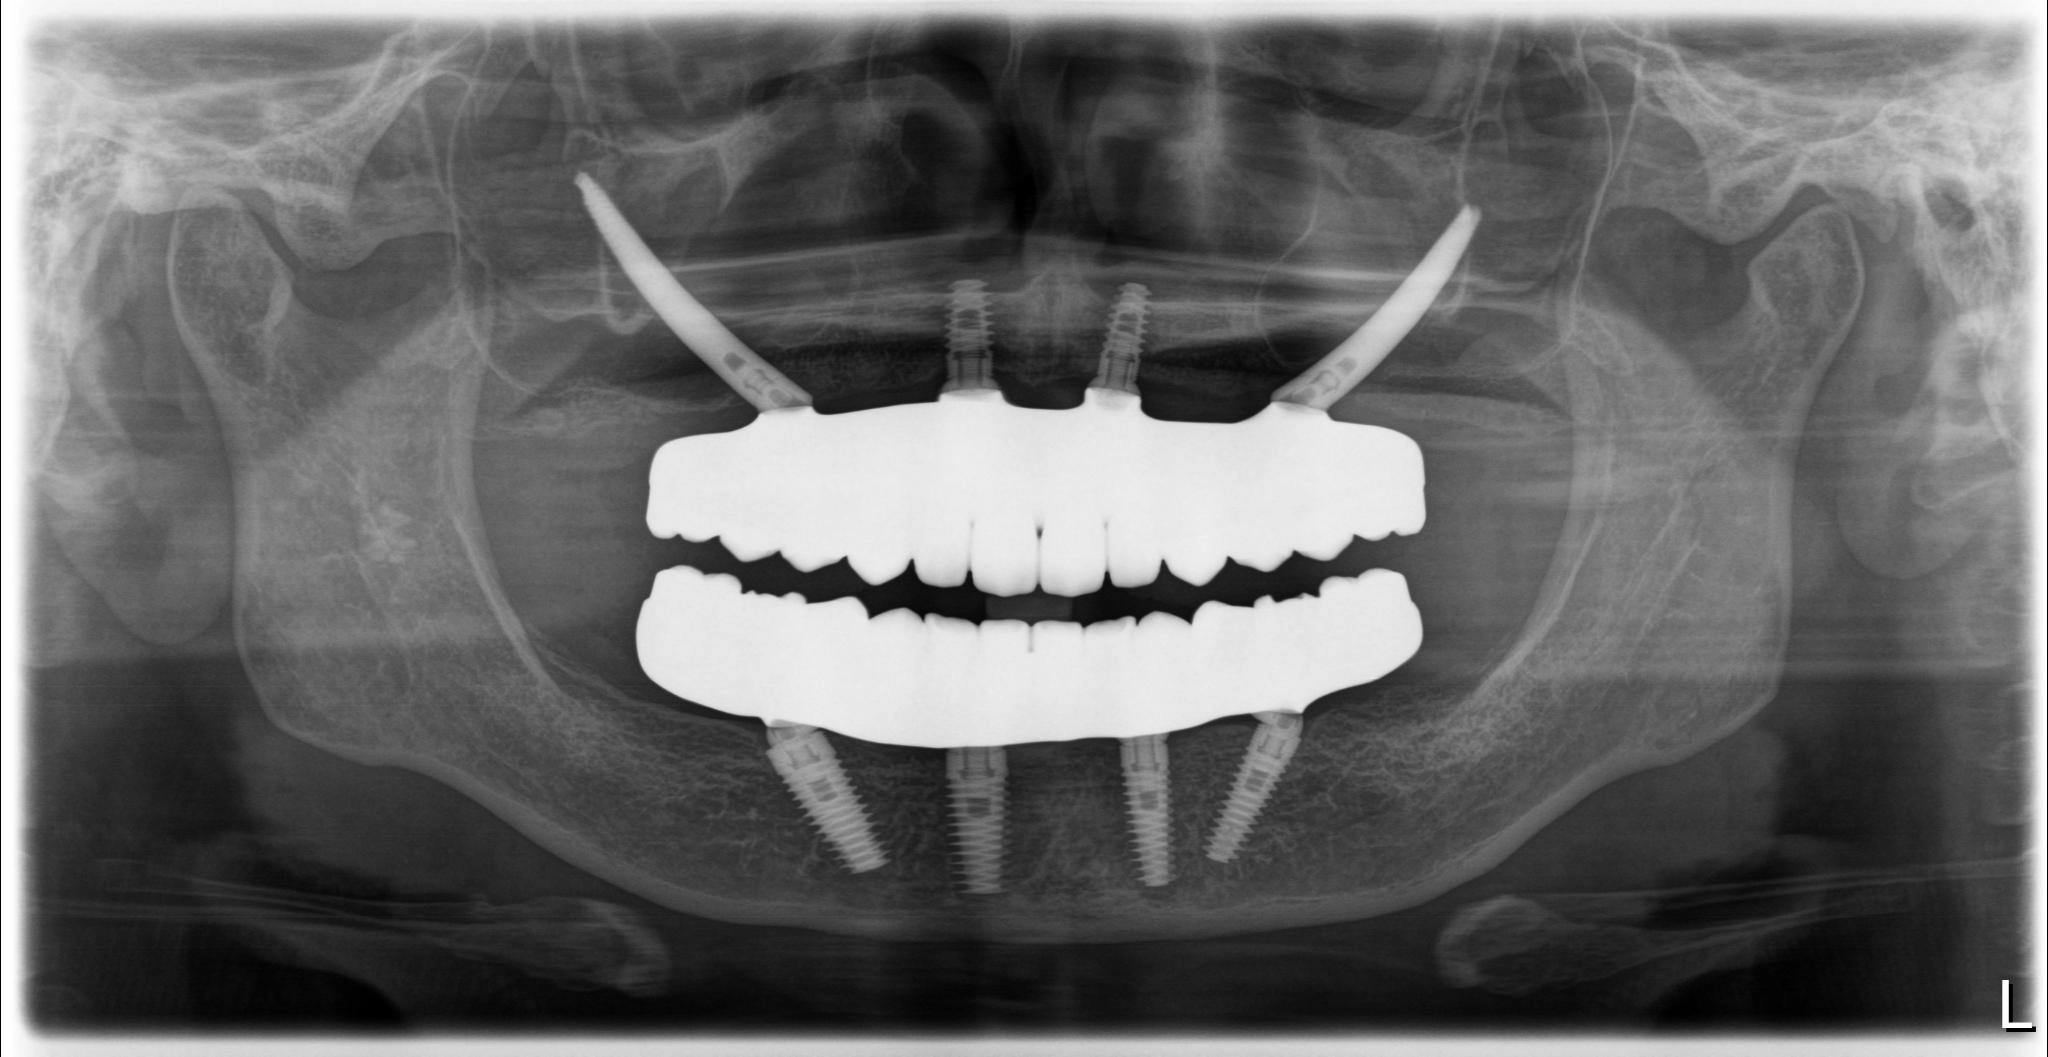

術後

内容 :上下顎オールオン4ザイゴマ2

費用 :5,899,850円

※モニター価格

期間 :半年

リスク:出血・腫れ・痺れ・痛み